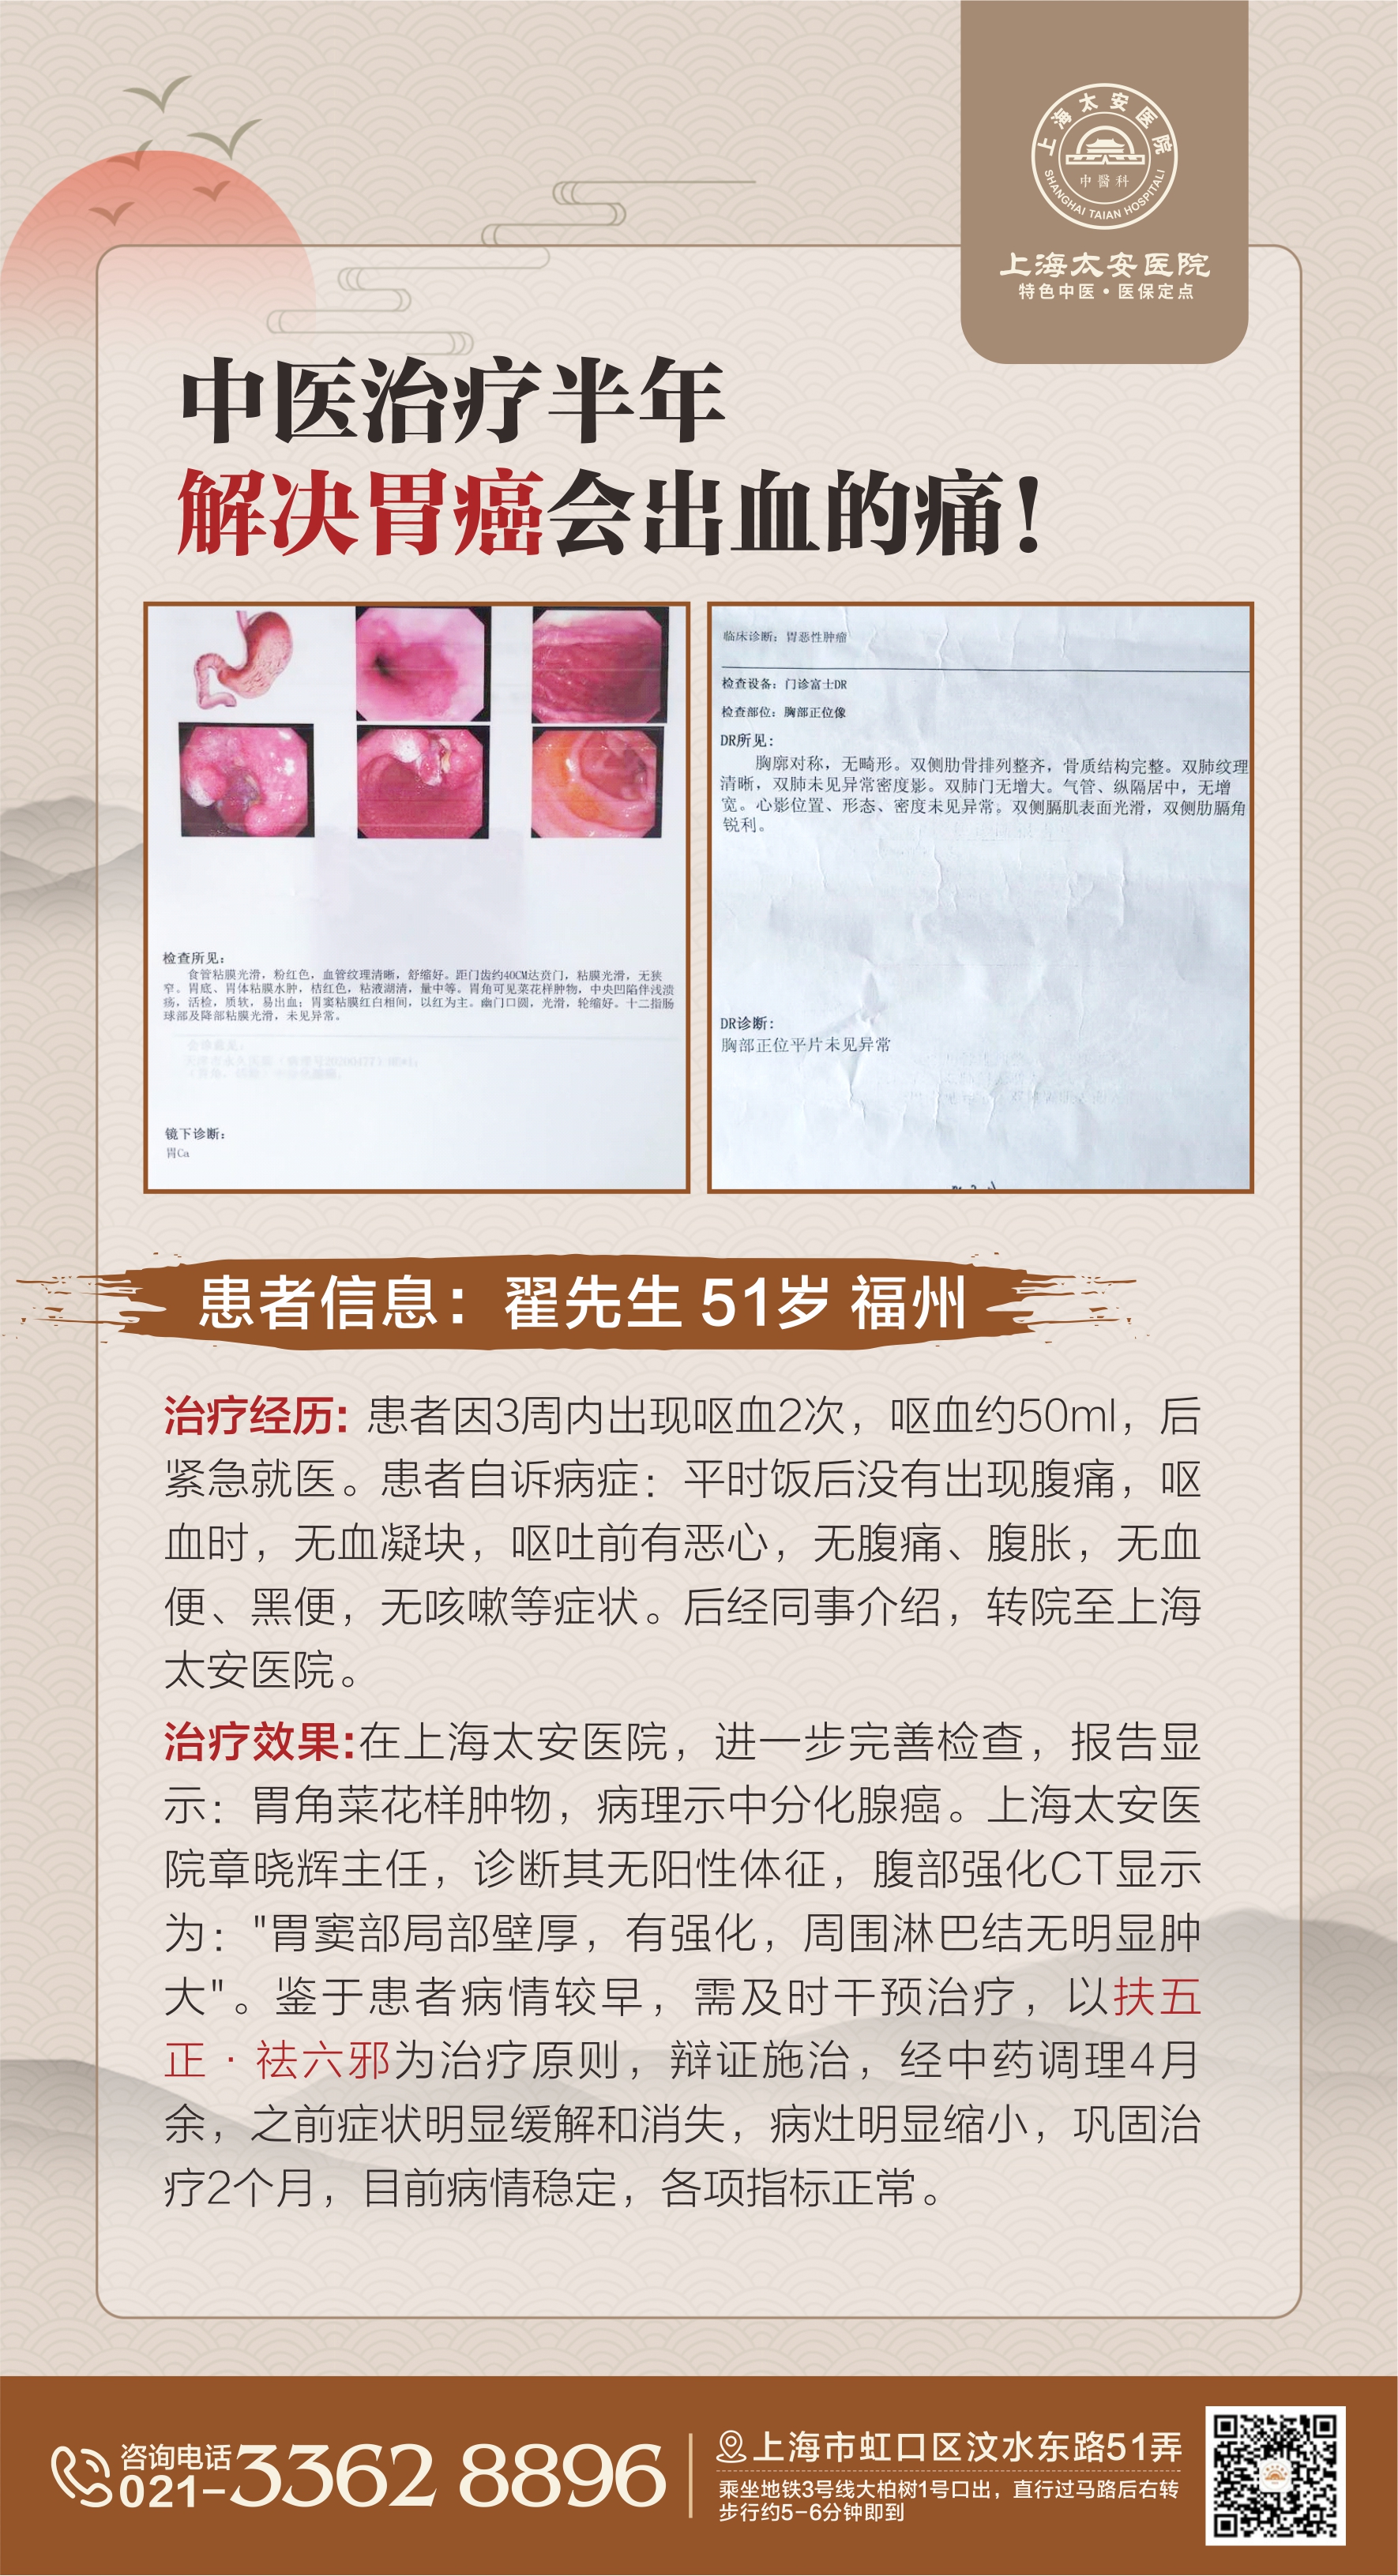

上海太安中医科内外结合

根据不同患者的病症、脉相等为依据,开具一人一方的特制中药组方,经设备作用于不同穴位。通过控释盘的正负加压作用下提供强大的给药动力,打通皮下组织层,建立连续给药通道,将药物经过穴位浸透毛细血管直接作用病灶深处,最大限度的提高药效。

动力温控经皮给药开启“抗癌消瘤”新纪元

再结合中药内调,形成内调、外治、内外结合的三重治疗方案具有安全、易操作、疼痛小易接受、累积刺激量大等特点。充分将中医整体护理理念进行融合,传统情志护理方法与经典外治技术相辅相成,互为促进。

动力温控经皮给药治疗遵循中医内病外治原理,体外给药效率3000倍以上,同时大幅度降低中药材毒副作用,从药方、药量、治疗部位、临床方案到最后疗效,均为标准化,可适用循证医学。

标本兼治:经临床应用证实,对肺癌、胰腺癌、胃癌、直肠癌、结肠癌、肝癌、喉癌等疾病实现标本兼治。